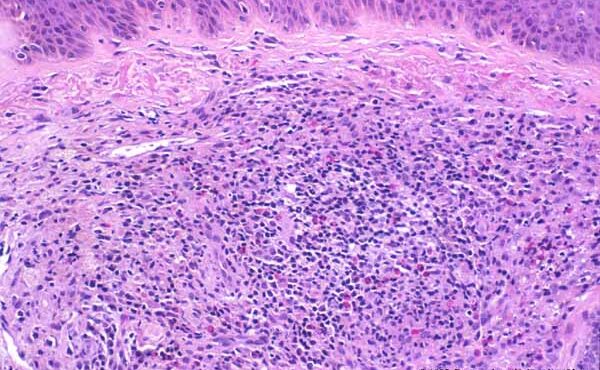

Graft versus Host Disease =داء رفض الطعم للمضيف Graft Versus Host Disease GVHD occurs in situations in which donor immunocompetent T cells transferred into allogenic hosts are incapable of rejecting them. The sources of the T cells include primarily peripheral blood stem cell and bone marrow transplants and, infrequently, unirradiated blood products , solid organ […]